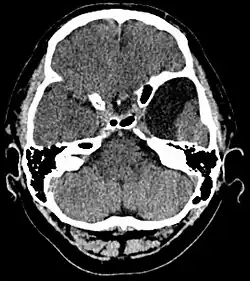

Arachnoidalzysten sind gutartige, zystische (flüssigkeitsgefüllte), zumeist angeborene Erweiterungen der Spinngewebshaut („Arachnoidea“, der mittleren Hirnhaut). Häufig sind sie ein Zufallsbefund bei der Computer- oder Magnetresonanztomographie des Kopfes.[1] Bei 1,7 % von 2536 gesunden männlichen Anwärtern für die deutsche Luftwaffe wurde mindestens eine Arachnoidalzyste diagnostiziert.[2] Eine Behandlung von Arachnoidalzysten ist nur zu erwägen, wenn sie Beschwerden machen, zum Beispiel bei Kompression von angrenzenden Gehirn- oder Rückenmarksanteilen. Arachnoidalzysten sind in der Regel Zufallsbefunde und können vollkommen symptomlos verlaufen, erst wenn es zu einer Kompression kommt, können die Betroffenen Symptome, wie Kopfschmerzen vernehmen. Treten Arachnoidalzysten bereits in der Wachstumsphase auf, können diese zu Schädeldeformationen führen.[3]